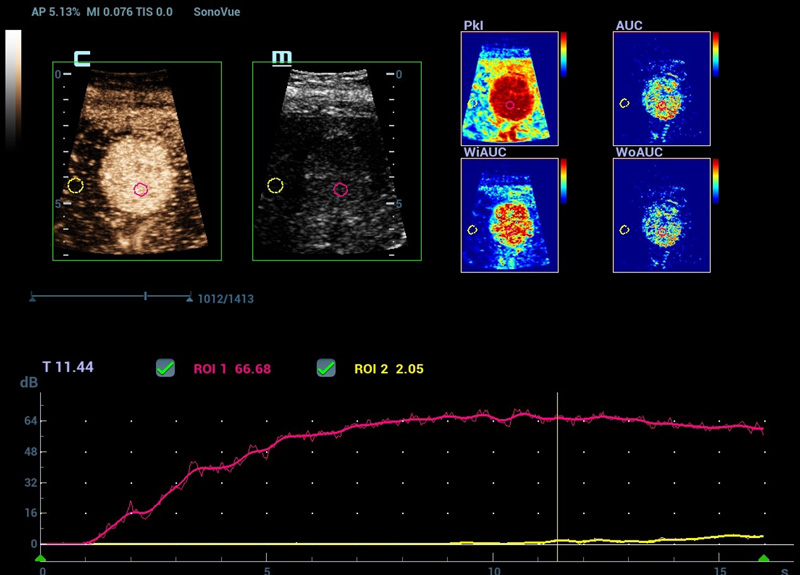

Nieuwe CEUS QA

Geavanceerde CEUS-kwantificatietools

Nieuwe CEUS-kwantificatieanalyse

Nieuwe CEUS QA Borst kwaadaardig

De tijd-intensiteitscurve maakt kwantitatieve analyse van CEUS-beeldvorming mogelijk. De nieuwe CEUS QA biedt tools voor geavanceerde kwantitatieve analyse die ondersteuning bieden bij tumorbeoordelingen en klinisch onderzoek.